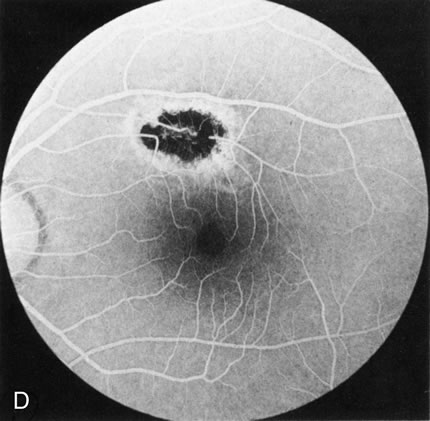

Fig. 1. Retinitis pigmentosa. A. A typical area of bone spicule pigmentation. B. Diffuse dye leakage is apparent throughout the posterior pole. C. The early angiogram shows dilated and irregular retinal radial peripapillary capillaries and perifoveal retinal capillaries. D. Leakage from these vessels are evident in the late angiogram.

Of more clinical importance is the role of FA in the diagnosis and treatment of cystoid macular edema (CME) (Fig. 1C and D). Stereoscopic FA indicates that the leakage, which may be diffuse or have the typical petaloid stellate appearance of CME, can come from the perifoveal retinal capillaries, from the choroid through the RPE, or from a combination of both sources.4 With the recent suggestion that CME in RP may be successfully treated with acetazolamide,5, 6 FA is thus important to document the diagnosis of CME, establish the origin(s) of leakage, and follow patients during and after therapy.